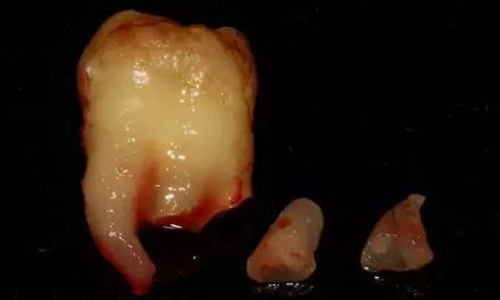

下面看一個病例,患者,女,30歲,因左下頜智齒嵌塞食物后疼痛,至當(dāng)?shù)匮揽平o予拔除,但術(shù)后1個半月,患者自覺拔牙區(qū)一直隱隱疼痛,時輕時重,遂來診。檢查發(fā)現(xiàn),拔牙創(chuàng)口一直未愈合,未見明顯腫脹,拍片發(fā)現(xiàn),拔牙窩內(nèi)顯示高密度斷根影

像,該斷根臨近下頜神經(jīng)管,同時發(fā)現(xiàn)第二磨牙遠中有兩塊高密度影像,疑似殘留骨片或牙片,應(yīng)該是引起疼痛的原因,經(jīng)與患者溝通,采納建議,進行二次拔牙。